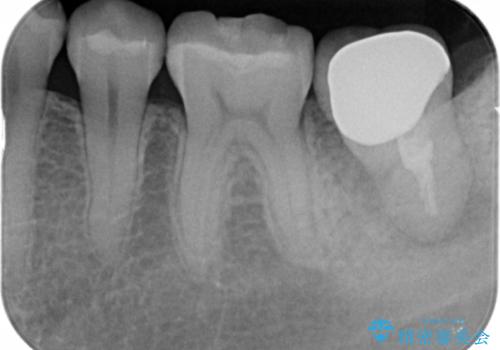

割れている奥歯を抜去後左上の機能していない親知らずを移植し、生着したのち根管治療・補綴を行いました。

インプラントや義歯を用いることなく咬合を回復することができ、喜んで頂けました。

治療期間も抜歯後3ヶ月以内かつ少ない来院回数(初診含めて6回)で治療を終えることができ、ご満足頂けました。

被せ物の種類:メタルボンドクラウン エコノミー フルベイク